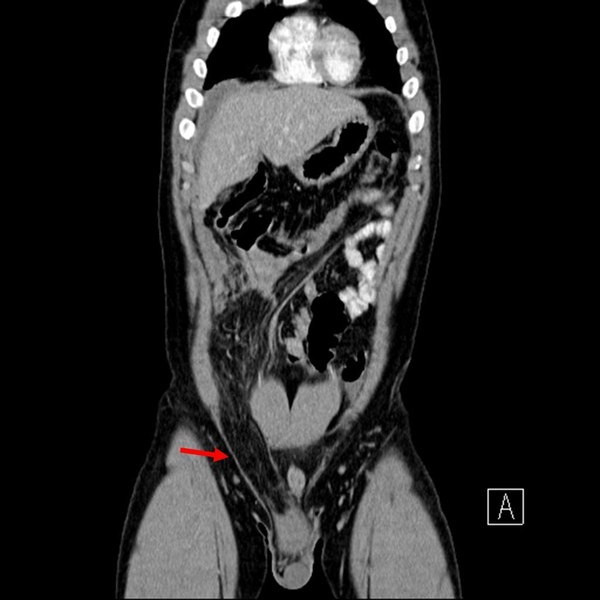

上圖紅色箭頭處圓圓大大黑黑的便是腹股溝疝氣,因為他疝氣囊裡的是大網膜,所以是黑色的一大坨。(小小複習:請問黃色箭頭指的是?您可以在男生女生大不同 裡找到答案。)

讓咱們換個切面來看,可以見到一長串墜入陰囊內的便是大網膜。從這張圖裡可以見到相當健壯的肌肉,可以推測是為壯年男性,或許是健身,或許是勞力工作,因使氣力會讓腹壓上升,加劇疝氣的程度。